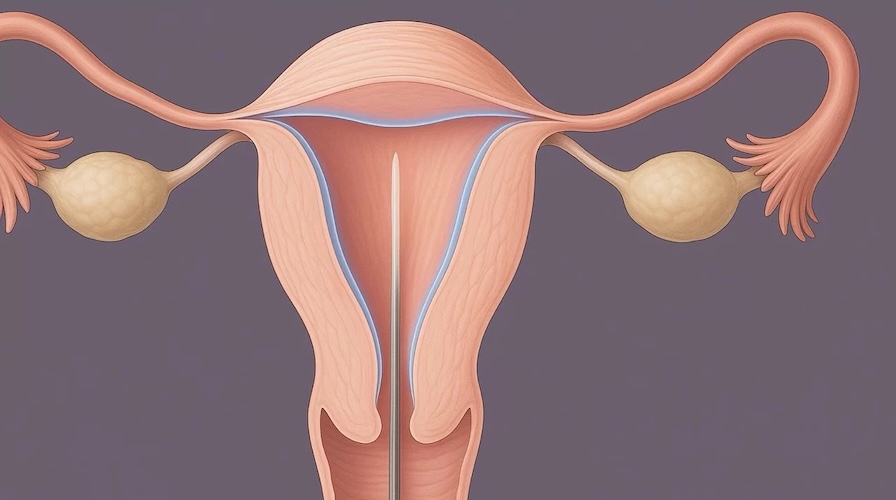

- Histeroscopía diagnóstica (método de elección)

La histeroscopía permite visualizar directamente la cavidad uterina y evaluar el grado de las adherencias.

- 🔬 Histeroscopía quirúrgica, para liberar las adherencias